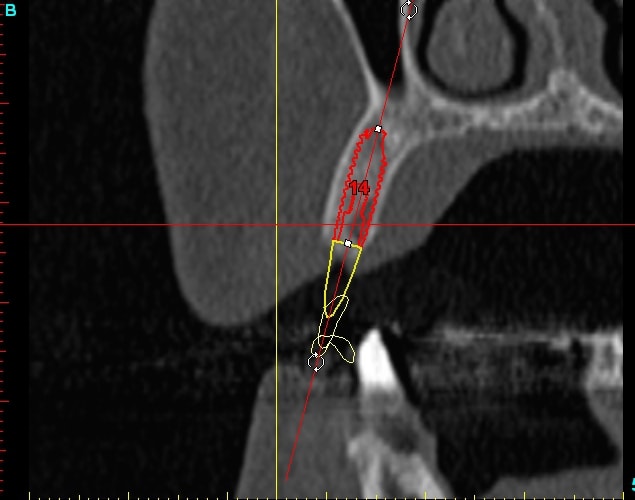

14dar tm9a6n - Eugenol

Dar14 mu6ia0 - Eugenol

15dar srylok - Eugenol

23dar fu8chl - Eugenol

Dar23 cngblb - Eugenol

24dar rfsfid - Eugenol

Dar24 scegbz - Eugenol

25dar yv2tvr - Eugenol